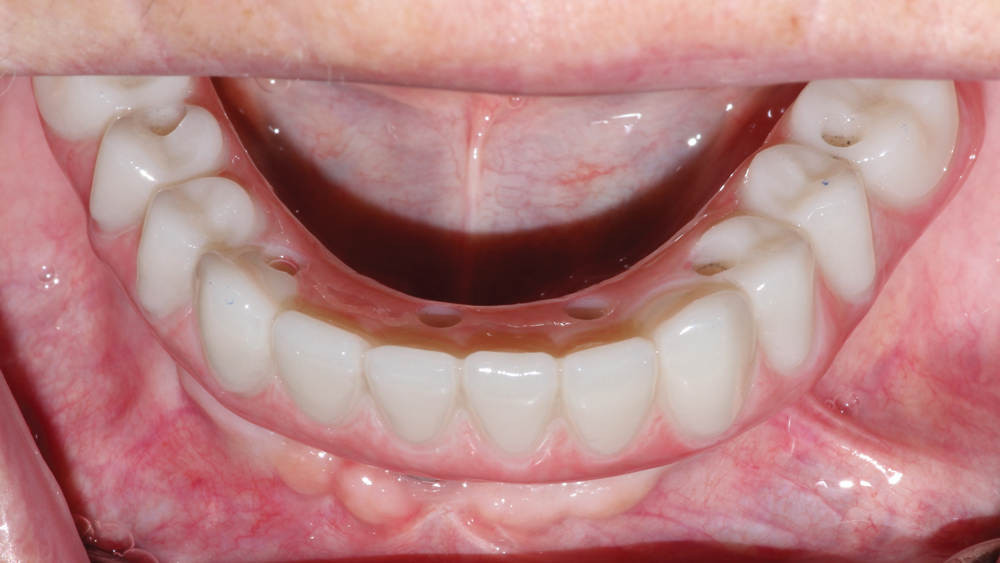

This patient was unhappy with the esthetics of her existing upper denture as well as the discomfort and instability caused by her loose-fitting mandibular partial denture. Although her concerns with the maxillary denture could be addressed with a new, more esthetic appliance, she preferred implant treatment for her mandible, where a fixed solution was needed to adequately restore function, stability and comfort.

Treatment plan:

The patient’s remaining mandibular teeth were extracted followed by immediate implant placement and delivery of a fixed provisional appliance. After integration of the implants, the prosthetic designs for the new upper denture and lower implant restoration were determined in tandem. Ultimately, the dual-arch restorations addressed the functional and esthetic challenges of the case while staying within the financial means of the patient, demonstrating the benefits of a flexible, multifaceted approach to restorative dentistry.